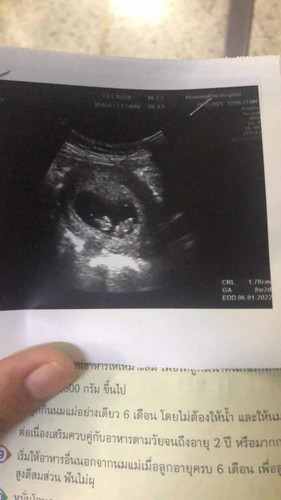

อยากรู้ว่าใบ้แฝดจริงไหมค้ะ👶🏻👶🏻 ไปซาวมาหมอบอกแฝด แต่ทางบ้านเราและสามีไม่มีใครมีแฝดเลย#ท้องแรกคะ

บ้านนี้ตอนซาวครั้งเเรกก็เเบบนี้เลยค่ะ บ้านนี้ก็แฝดค่ะ ตอนนี้21w1dเเล้วค่ะ รูปตอนซาวครั้งเเรก ทางบ้านทั้งสองฝ่ายไม่มีเเฝดเหมือนกันค่ะเเบบนี้เขาเรียกว่าเเฝดเหมือนค่ะ เพศเขาจะเหมือนกันไม่มีโอกาสเพศต่างกันหน้าตาจะเหมือนกันมากค่ะ เกิดจากอาสุจิ1ตัวเขาเเบ่งงเซลเป็น2ตัวค่ะ บ้านนี้ได้เเฝดญ/ญค่ะ

หมอบอกว่าใช่ ก็คงใช่ค่ะแน่นอนอยู่แล้ว และดูจากรูปก็ใช่อยู่ดี

ดูเหมือนจะแฝดจริงๆนะคะ ยินดีกับคุณแม่ด้วยค่าา😊